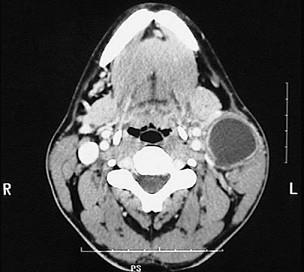

图示是鳃裂囊肿患者的CT 检查结果,关于此病的描述错误的是 ( )

A可形成瘘

B可继发感染

C大小不定,生长缓慢

D无自觉症状

E触之有搏动感